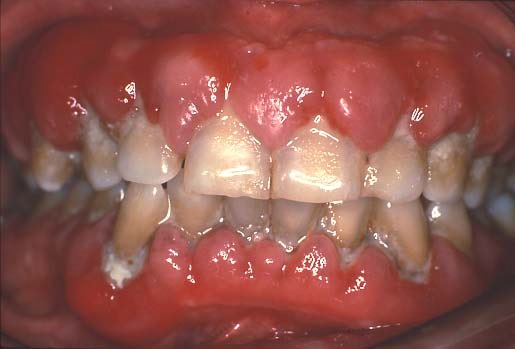

Inflammatory Gingival Enlargement

The gingival enlargement observed may be localized or generalized and is an inflammatory response that occurs when plaque (collection of food debris and bacteria) accumulates on the teeth. This is a result of the patient not accomplishing effective oral hygiene. An example is noted to the right. Gums affected by this condition are often tender, soft, red, and bleed easily. Fortunately, this condition usually resolves with effective oral hygiene practices (tooth brushing, flossing) to remove the plaque and irritants on the teeth.